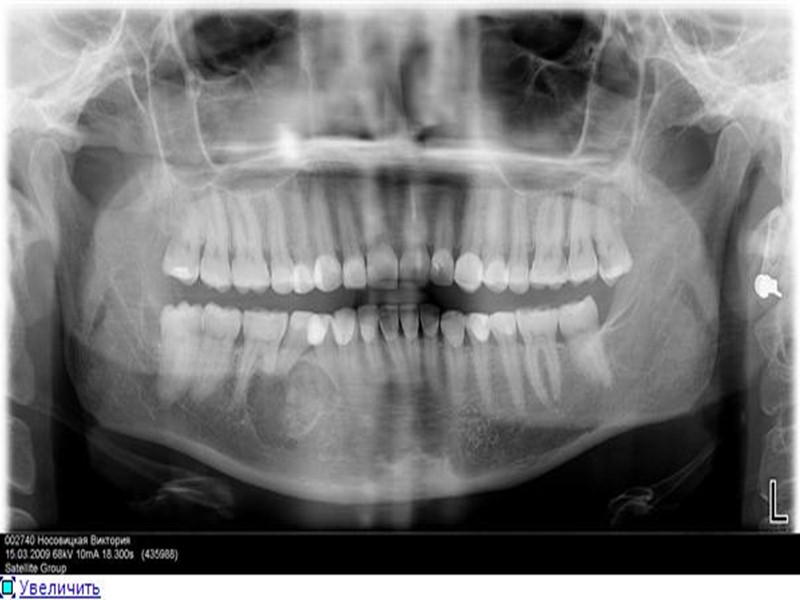

На рентгенограмме челюсти определяется лишенный структуры участок кости, имеющий более или менее четко очерченные границы. Корни соседних зубов оказываются отодвинутыми. Костная граница периодонтальной щели зуба, от которого растет киста, разрушена и потому на рентгенограмме не контурируется. При пункции кистозной полости (толстой иглой) получают янтарно-светлую жидкость с примесью холестериновых зерен – блесток. симптомы: внешне заметная деформация кости; симптом пергаментного хруста, продавливаемой пластмассовой или резиновой игрушки; еще симптом флюктуации; наличие специфического пунктата (янтарный цвет, блестки холестерина); дивергенция корней зубов. В случае нагноения ко всем этим объективным симптомам присоединяются покраснение, отечность и инфильтрация окружающих тканей, а также жалобы больных на более или менее выраженную боль в области кисты и повышение температуры тела. Если нагноение содержимого кисты переходит в острый остеомиелит челюсти, появляются симптомы этого заболевания.